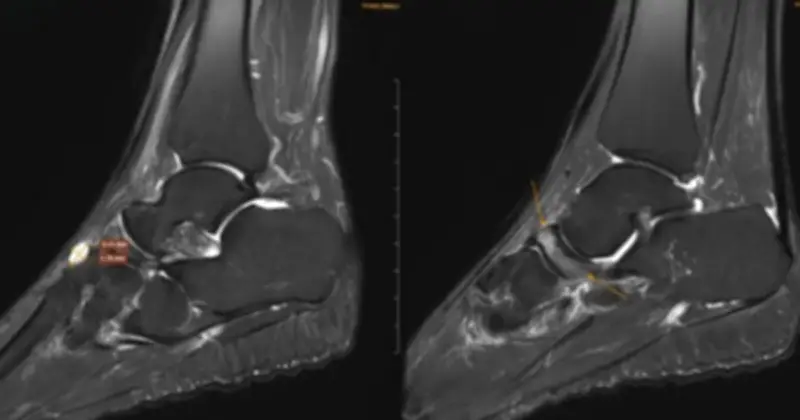

Để xác định nguyên nhân chính xác, các bác sĩ đã chỉ định chụp cộng hưởng từ (MRI). Kết quả cho thấy xương ghe bị xẹp và biến dạng điển hình với hình dạng “dấu phẩy”, kèm theo hiện tượng đặc xương dưới sụn và phù tủy xương rõ rệt. Ngoài ra, nhiều tổn thương phối hợp khác cũng được ghi nhận, bao gồm:

- Gai xương

- Phù dây chằng

- Tràn dịch khớp cổ chân

Dựa trên các dấu hiệu lâm sàng và hình ảnh học, bệnh nhân đã được chẩn đoán theo dõi Hội chứng Mueller-Weiss ở chân phải và phù tủy xương sên trái.